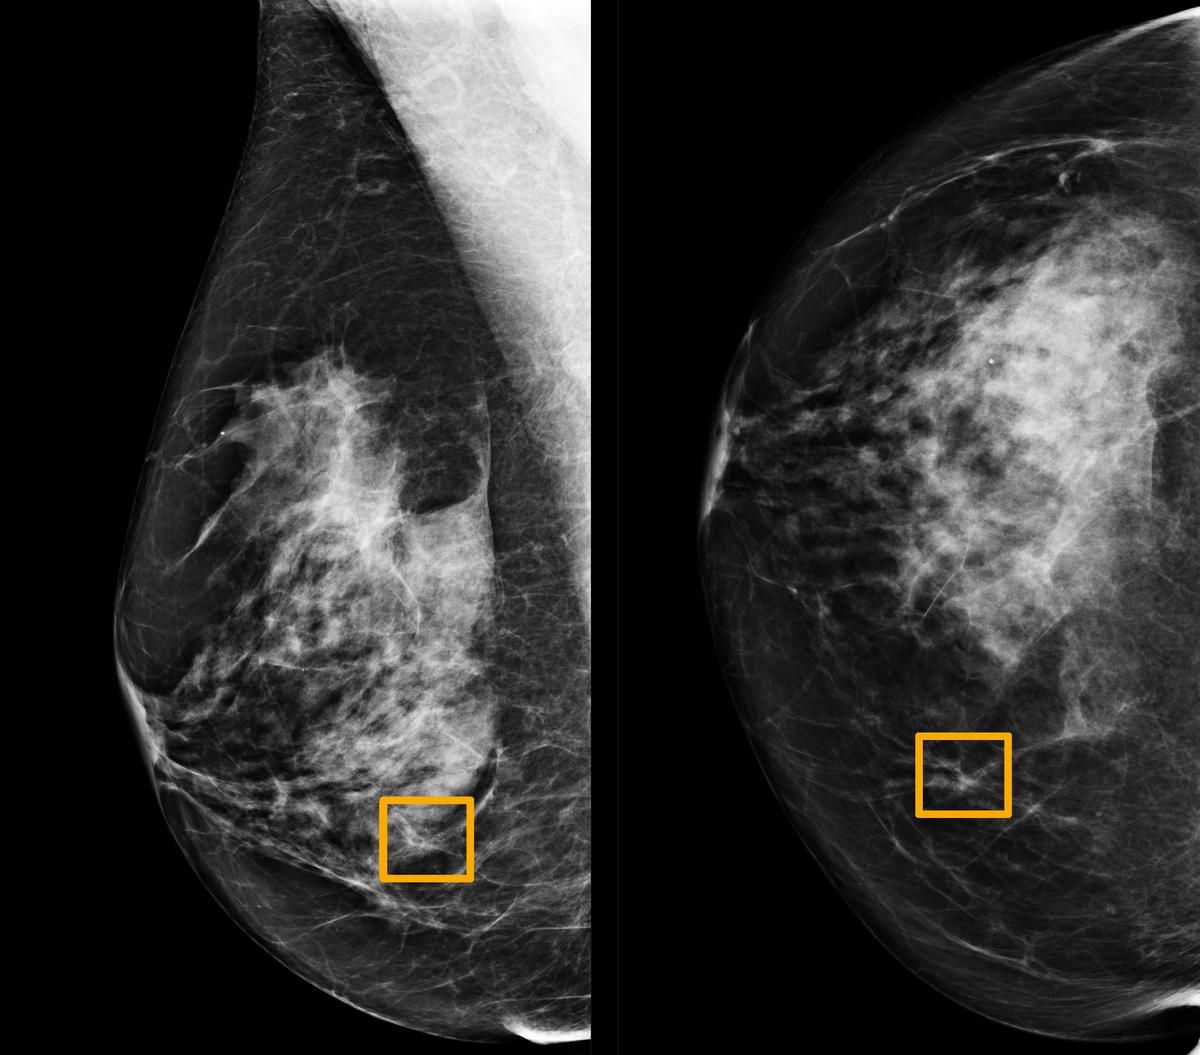

🎗 Artificiell Intelligens ökar träffsäkerheten vid diagnos av bröstcancer

Ett AI-system ger lika bra eller bättre resultat än radiologer vid upptäkt av bröstcancer vid analys av mammogram.